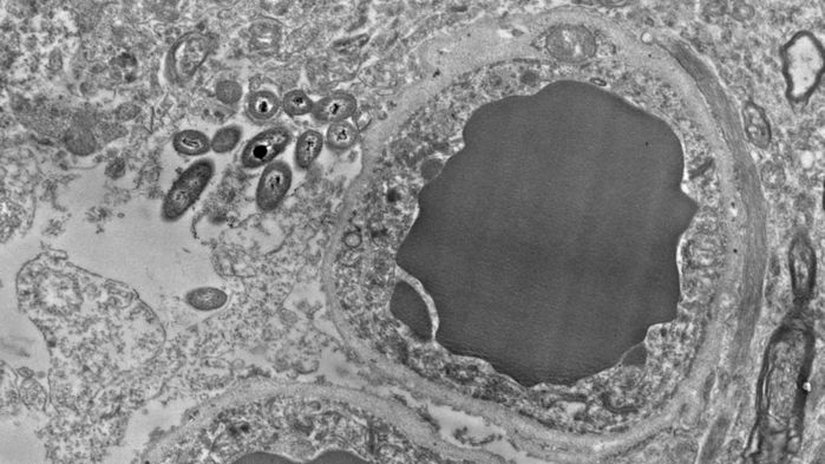

Neuroscience dergisinde yayımlanan bir araştırmada ise nörolojik anlamda sağlıklı bir insanın beynindeki yüksek çözünürlüklü (TEM) görüntüleme yöntemi sayesinde bakterilerin kan damarı yanında görüntülenmesi sağlandı!

Yukarıdaki fotoğrafta, her nasılsa, hiçbir sorun yaşamadan bakterilerin o bölgeye ulaştığı görülüyor. Elbette bu çalışma henüz başlangıç olduğu için üzerinde kesin bir tanıya varmak zor. Fakat oldukça ilginç, bilimsel soruların doğmasını sağlayabilir.

Elbette bu fikir eskiden de mevcuttu. Hatta birçok bilim insanı bu konu hakkında önemli çalışmalar yapmıştır. Makrofajlar ile lenfatik sistem yoluyla beyin bölgesine taşındığı biliniyordu. Fakat elektron mikroskobu ile ilk doğrudan gözlem olması, bu çalışmayı özel kılmaktadır.

Şunu belirtmekte fayda var: Alınan histolojik görüntü bir kadavraya (eğitim/inceleme amacı ile kullanılan ceset) ait. Yani bakteriler bedene sonradan dahil olmuş veya savunma sisteminin işlevini sonlandırması sonucu beyne ulaşmış olabilirler. Yine de şu ana kadar sayısız kadavrada incelendi; fakat bu şekilde herhangi bir gözlem yapılamamıştı.

Peki neden şimdiye kadar herhangi bir beyin kesitinde görülmediler? Çünkü nadiren bir postmortem (ölüm sonrası) beyin, elektron mikroskobu altında incelenir. Bakteriler de fazlası ile küçük olduklarından dolayı, ışık mikroskobunda tespit edilmeleri çok zordur.